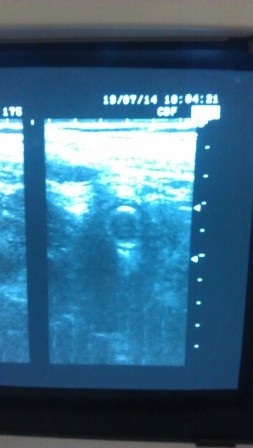

Qua kết quả siêu âm cho thấy xuất hiện hiện tượng phù nề, xét nghiệm cận lâm sàng và chuẩn đoán bệnh nhân bị viêm ruột thừa cấp kèm theo tăng huyết áp.